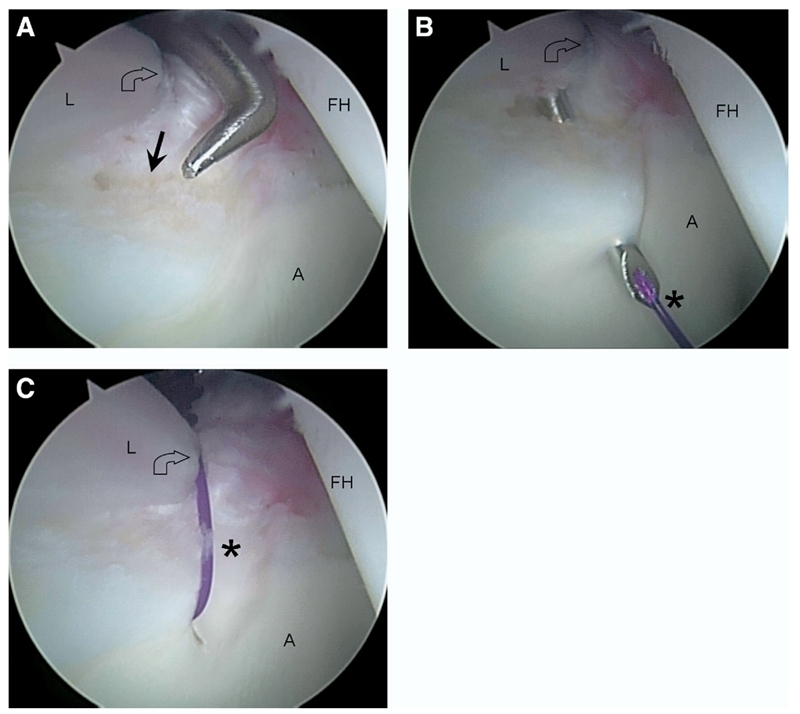

图4.(A)髋臼撞击症在股骨头颈交界处的撞击性骨病变(箭头)的关节镜图像,其特征是与盂唇(L)邻接并导致(现已修复的)盂唇撕裂(星号)。

(B)病变的关节镜下磨锉骨成形术(闭合箭头可)减轻盂唇撞击。

(C)屈曲髋关节的关节镜图像,显示关节镜下磨锉骨成形术(闭合箭头)后盂唇(L)撞击减轻。星号表示盂唇修复。